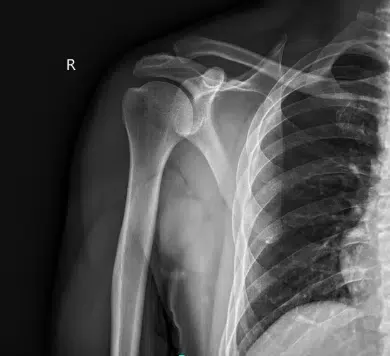

Presentó los resultados de la radiografía del hombro derecho que mostraron artropatía de la articulación acromioclavicular. En la cadera izquierda, las radiografías han mostrado una leve sobrecobertura acetabular. Para la columna cervical, reducción leve del espacio discológico.

Radiografía del hombro derecho mínimo 2 vistas